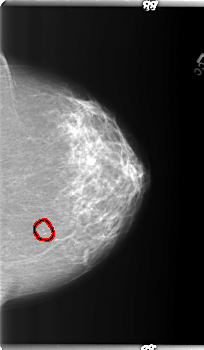

FILE: B_3367_1.LEFT_CC.OVERLAY

TOTAL_ABNORMALITIES 1

ABNORMALITY 1

LESION_TYPE CALCIFICATION TYPE PLEOMORPHIC DISTRIBUTION CLUSTERED

ASSESSMENT 4

SUBTLETY 3

PATHOLOGY BENIGN

TOTAL_OUTLINES 1

BOUNDARY

LEFT_CC LINES 5936 PIXELS_PER_LINE 3456 BITS_PER_PIXEL 12 RESOLUTION 50 OVERLAY